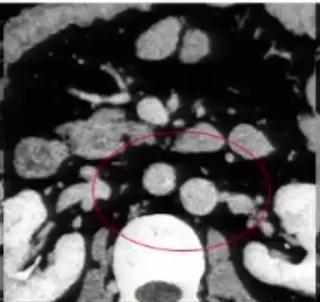

图2:冠状位重建显示下腔静脉肝段和肝下段缺如,向上直接延续为奇静脉

肾癌伴血管结构畸形

肾癌伴血管结构畸形患者的血管结构畸形往往容易被忽视。 在手术的过程中,如不注意就可能造成肝右叶血流的回流障碍,导致严重的临床后果。